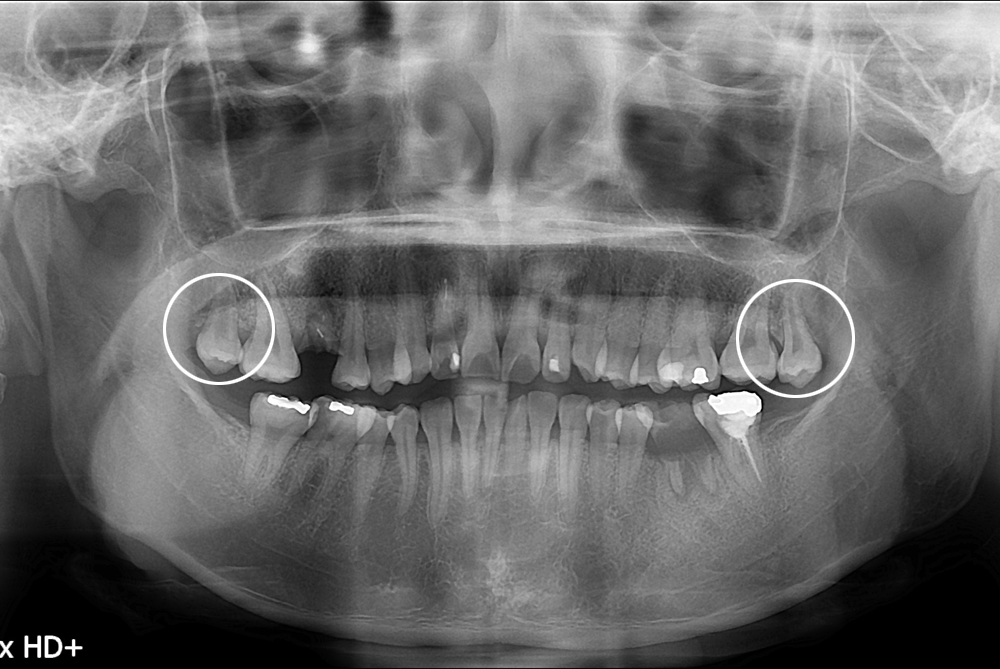

[사랑니] 난발치 사랑니 발치

치료전 : 2017-08-10